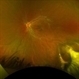

- toxocara granuloma

- Fundus photo showed central posterior granuloma on the optic nerve